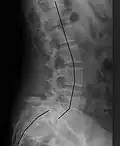

X-ray of measurement of spondylolisthesis at the lumbosacral joint, being 25% (grade 1) in this example -

X-ray picture of a grade 1 isthmic anterolisthesis at L4-5 -

Classification by degree of the slippage, as measured as percentage of the width of the vertebral body:[17] Grade I spondylolisthesis accounts for approximately 75% of all cases.[7]

- Grade I: 0–25%

- Grade II: 25–50%

- Grade III: 50–75%

- Grade IV: 75–100%

- Grade V: greater than 100%